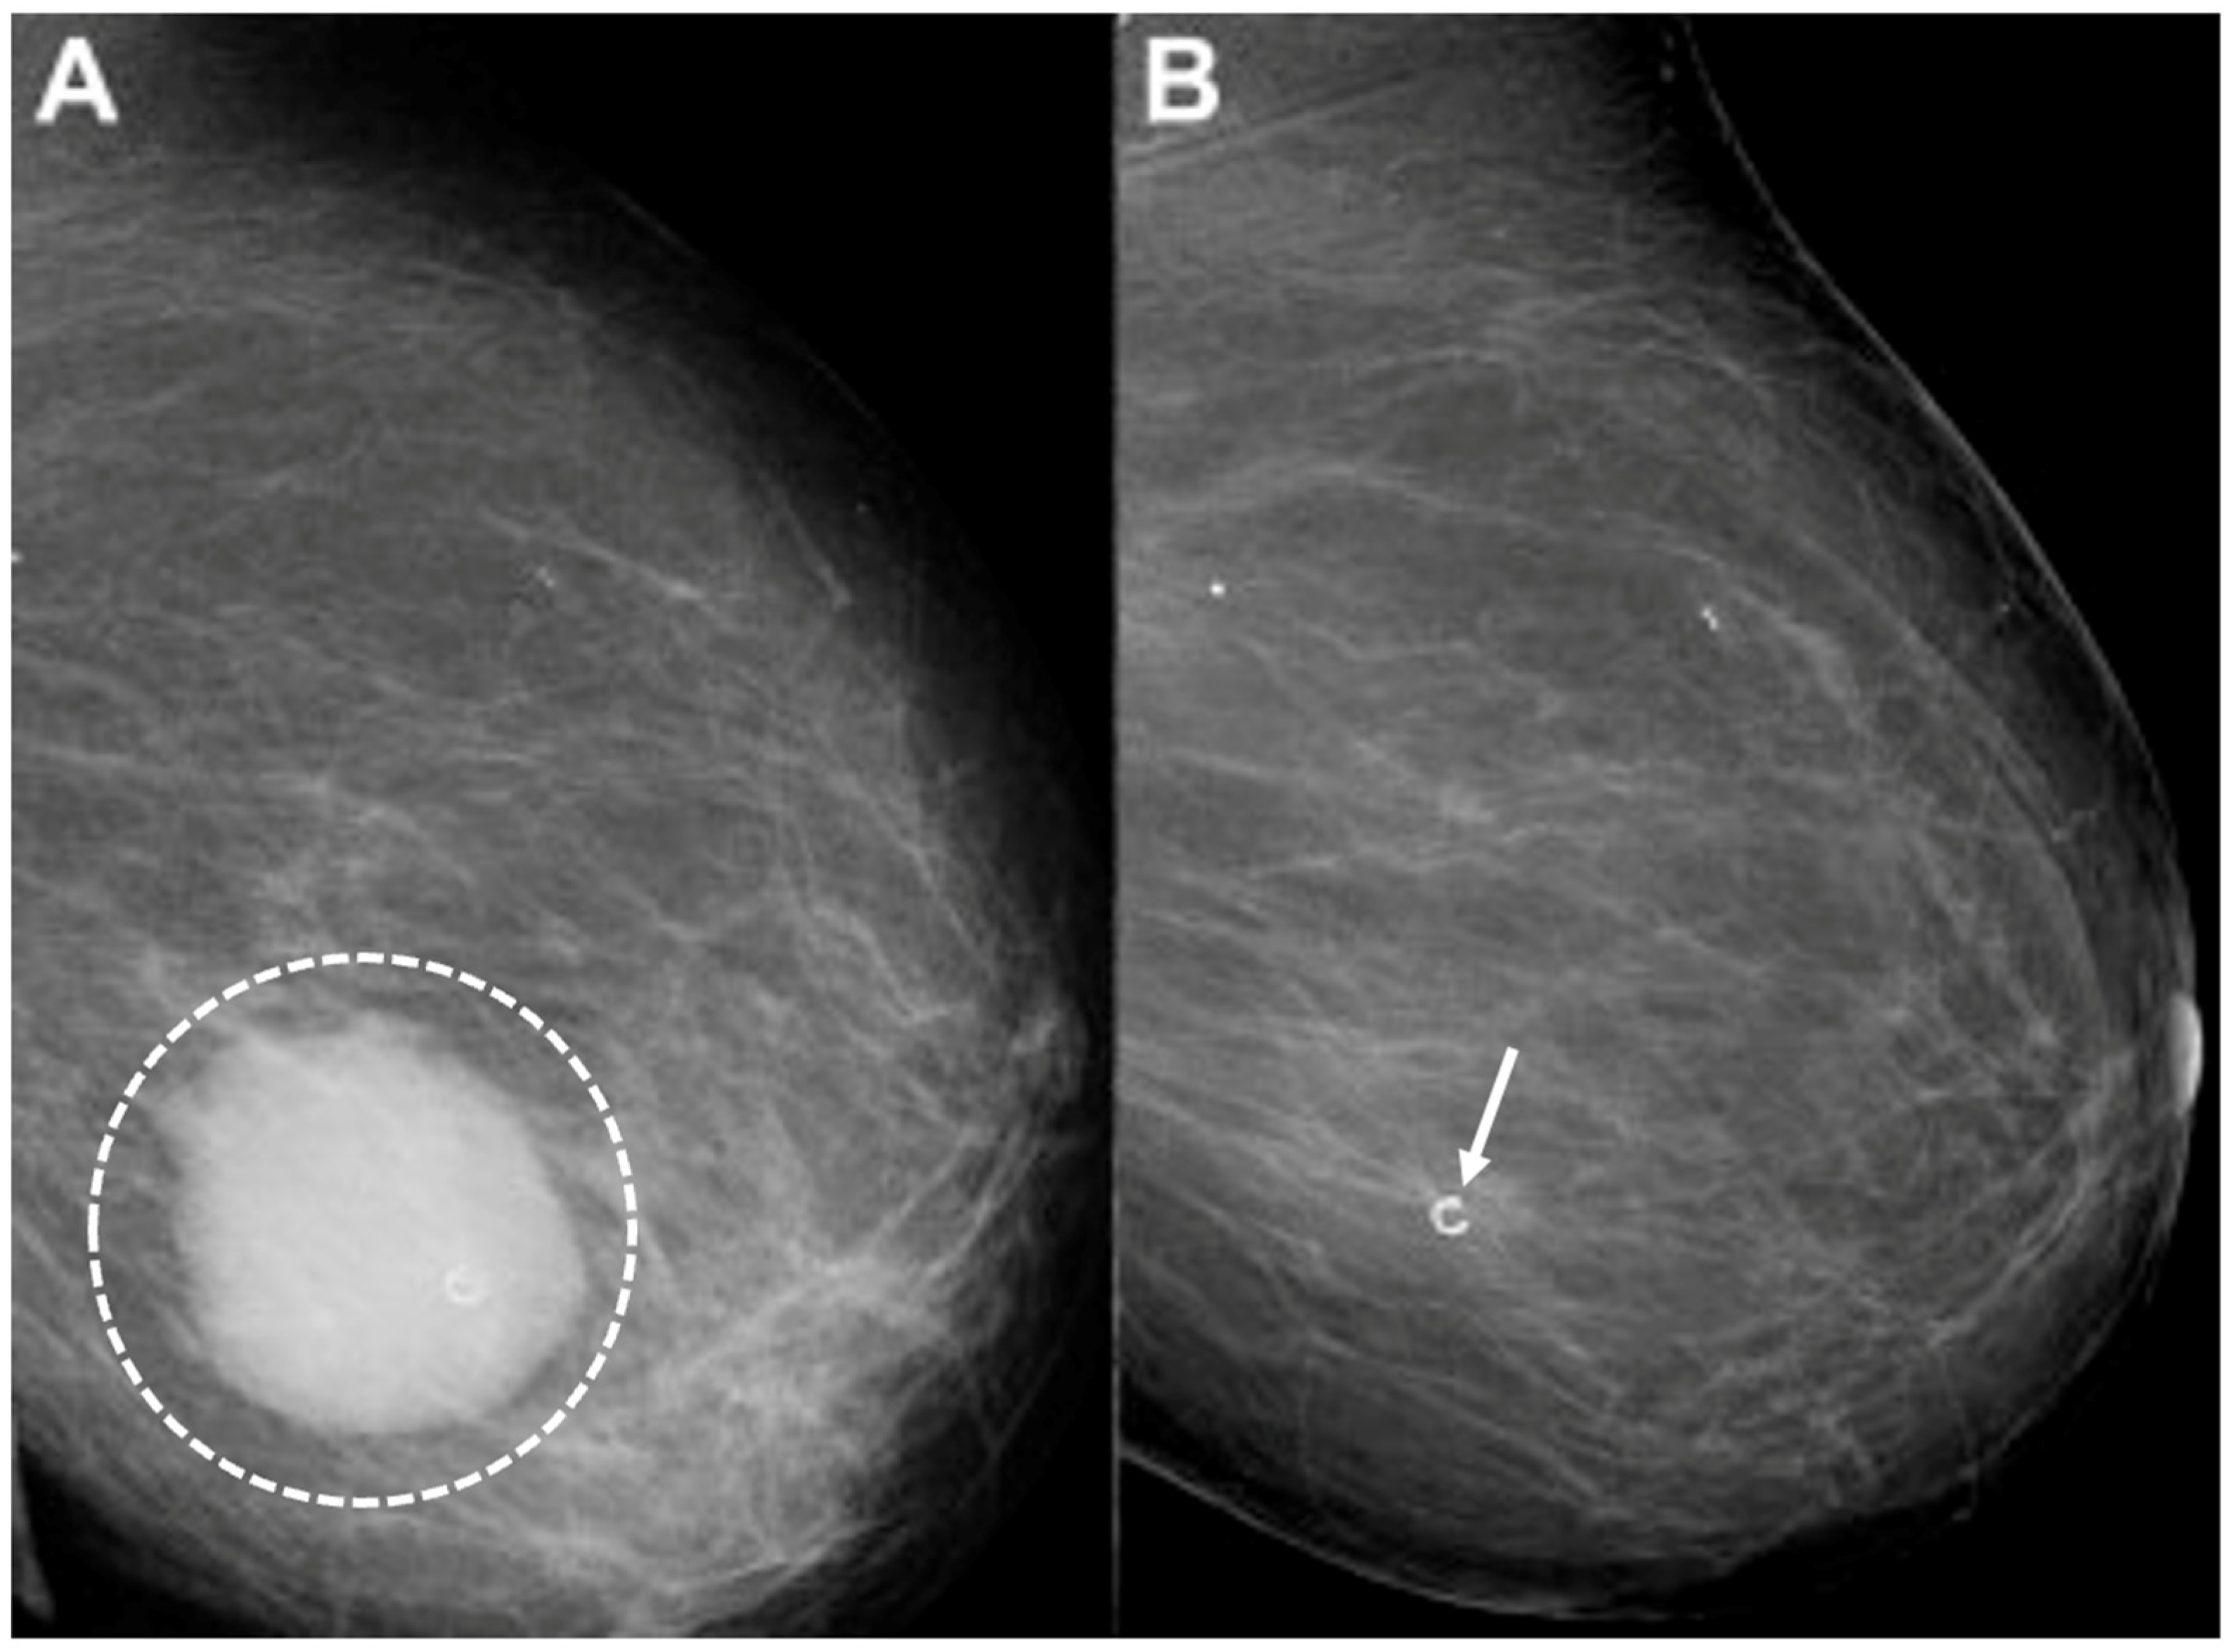

Digital Mammography. Breast cancer staging should include bilateral digital diagnostic mammograms (preferably 3D mammograms or tomosynthesis) to evaluate the extent of disease. Although cryoablation is generally performed under ultrasound or CT-scan guidance, high-quality mammography might reveal additional areas of cancer in the same region of the breast (multifocal cancer) or in a different region of the breast (multicentric cancer) that might impact patient selection or alter the cryoablation treatment plan. Multicentric and multifocal breast cancer is generally regarded as a contraindication to cryoablation. Pre-treatment assessment of the mammograms should seek the detection of spiculations (radial tumor extensions) and/or microcalcifications that might reach beyond the main tumor mass and require incorporation in the cryoablation treatment zone (Figure 1). Since mammography is the only imaging study that reliably shows microcalcifications, mammography plays a particularly important role in determining disease extent when suspicious microcalcifications are part of the disease process. Consequently, patients who are generally opposed to obtaining screening mammograms should be encouraged to have at least one set of pre-treatment diagnostic mammograms to exclude the presence of suspicious microcalcifications that could impact patient selection and/or treatment planning.

Figure 1.

Mammogram showing density corresponding to a palpable mass (see dashed lines) as well as suspicious microcalcifications (arrows) and inset image showing magnified view of white punctate calcifications extending beyond the palpable mass.